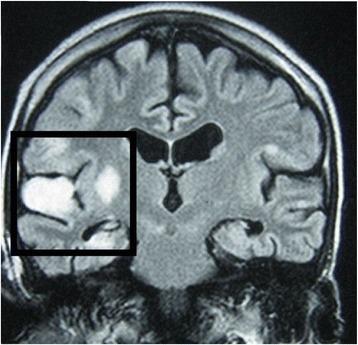

A 17-year-old adolescent boy of Sri Lankan Moor heritage was taking long-term immunosuppressants for nephrotic syndrome. He presented to hospital with focal fits affecting his left arm. He later developed choreiform movements of the same arm, progressing to epilepsia partialis continua and weakness. The gradually evolving focal neurological signs and underlying immunosuppression raised the possibility of localized cerebral infection or inflammation. Analysis of his cerebrospinal fluid showed lymphocytosis with normal cellular morphology. Magnetic resonance imaging was suggestive of progressive vasculitic infarctions of the cerebral cortex and basal ganglia. There was no evidence of active autoimmune or viral disease on hematological investigations, but molecular amplification detected Mycobacterium tuberculosis in his cerebrospinal fluid. Although our patient had been established on isoniazid preventive treatment for eight months before the episode, tuberculosis was nonetheless considered to be the most likely cause of the cerebral vasculitis. He was treated with a trial of anti-tuberculosis treatment, including streptomycin and adjunctive steroids, and made an uneventful recovery.

一名17岁具有斯里兰卡摩尔族血统的青少年男性因肾病综合征长期服用免疫抑制剂。他因左臂局灶性抽搐入院。随后该手臂出现舞蹈样动作,进而发展为持续性部分性癫痫发作和无力。逐渐演变的局灶性神经体征及潜在的免疫抑制提示存在局限性脑感染或炎症。其脑脊液分析显示淋巴细胞增多,细胞形态正常。磁共振成像提示大脑皮质和基底节区进行性血管炎性梗死。血液学检查未发现活动性自身免疫性或病毒性疾病证据,但分子扩增检测在其脑脊液中发现结核分枝杆菌。尽管我们的患者在此次发作前已接受异烟肼预防性治疗8个月,但结核病仍被认为是脑血管炎最可能的病因。他接受了包括链霉素和辅助性类固醇在内的抗结核治疗试验,恢复过程顺利。